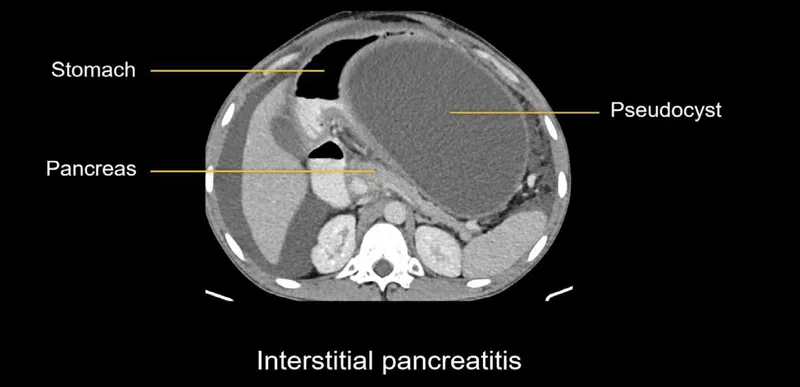

- Imaging:

- USG Abdomen: Initial (to detect gallstones).

- CECT: Best for diagnosis confirmation (if unclear), assessing severity (e.g., necrosis), and detecting complications (usually 48-72 hours after onset if indicated).

- Local Complications:

- Acute Peripancreatic Fluid Collection (APFC)

- Pancreatic Pseudocyst (>4 wks, encapsulated fluid, defined wall)

- Acute Necrotic Collection (ANC)

- Walled-Off Necrosis (WON) (>4 wks, encapsulated necrosis ± debris)

- Infected necrosis (critical)

- Pancreatic abscess